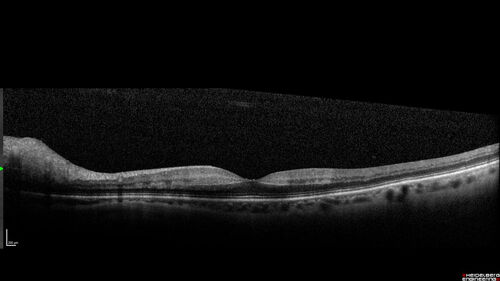

Central Retinal Vein Occlusion with cilioretinal artery occlusion

63 year old female who lost vision in the left eye 2 days ago. She was in the emergency room and had a lot of tests done which were all reportedly normal. The right eye is OK.

VA OD: Dcc20/25 NccJ2

VA OS: Dcc20/200-1 PHNI Ncc20/400-1

IOP: TP: OD:11 OS:12